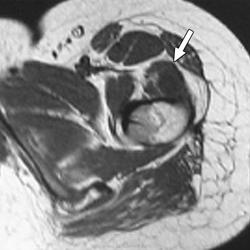

Юкстакортикальная хондросаркома (син.: паростальная хондросаркома, периостальная хондросаркома)—довольно редкая злокачественная опухоль, которая составляет 2 % от общего числа хондросарком. До 80 % больных находятся в возрасте старше 20 лет и лишь 1/3 из них предъявляют жалобы на боль. Опухоль постепенно увеличивается в размерах в течение многих месяцев. Наиболее частая ее локализация — метафизарая часть бедренной кости. Реже поражаются плечевая кость, кости таза, очень редко —ребра и кости стопы. Рентгенологическая картина напоминает то, что характерно для периостальной хондромы с ее блюдцеобразным вдавлением и склерозированным краем в пораженной кости. В некоторых случаях обнаруживается частичное разрушение кортикальной пластинки, и тогда граница опухоли с окружающей костью становится расплывчатой. На границе опухоли с непораженной костью часто видна треугольная склеротическая шпора. Юкстакортикальная хондросаркома часто достигает больших размеров: 7—17 см в диаметре. При осмотре невооруженным глазом юкстакортикальная хондросаркома имеет вид дольчатого новообразования беловато-серого цвета, полупрозрачного на разрезе. На поверхности разреза часто встречается очаговое обызвествление. Подлежащая кортикальная пластинка разрушена и замещена склерозированной костной тканью. Опухоль никогда не проникает в костномозговой канал, хотя под надкостницей она разрастается очень широко.

Под микроскопом отдельные дольки, состоящие из зрелого гиалинового хряща, окружены тонкими фиброзными прослойками, которые местами имеют миксоидный вид, или костными балками (по типу костной метаплазии). Опухолевые клетки лишены способности продуцировать остеоид. Степень злокачественности юкстакортикальной хондросаркомы обычно 1-я или 2-я. Обычно обнаруживается инвазия опухоли в мягкие ткани.

Периостальная хондросаркома встречается очень редко. Она подразделяется на истинно периостальную хондросаркому, когда вся опухоль располагается на наружной и на внутренней поверхностях надкостницы. Опухоли не имеют клинически четкой границы, поэтому при попытках иссечения только участка надкостницы опухоль обычно рецидивирует.

Мы наблюдали женщину 56 лет, которой опытные хирурги иссекали надкостницу с опухолью в нижней трети лучевой кости, и оба раза наступали рецидивы. Нами была произведена резекция нижнего конца обеих костей предплечья с замещением дефекта; хороший эффект отмечен в течение 26 лет. Рецидивы при иссечении надкостницы объясняются, по нашему мнению, тем, что невозможно определить, какую часть окружности кости поразила опухоль и где она проросла в кортикальный слой. Необходима компьютерная томография.